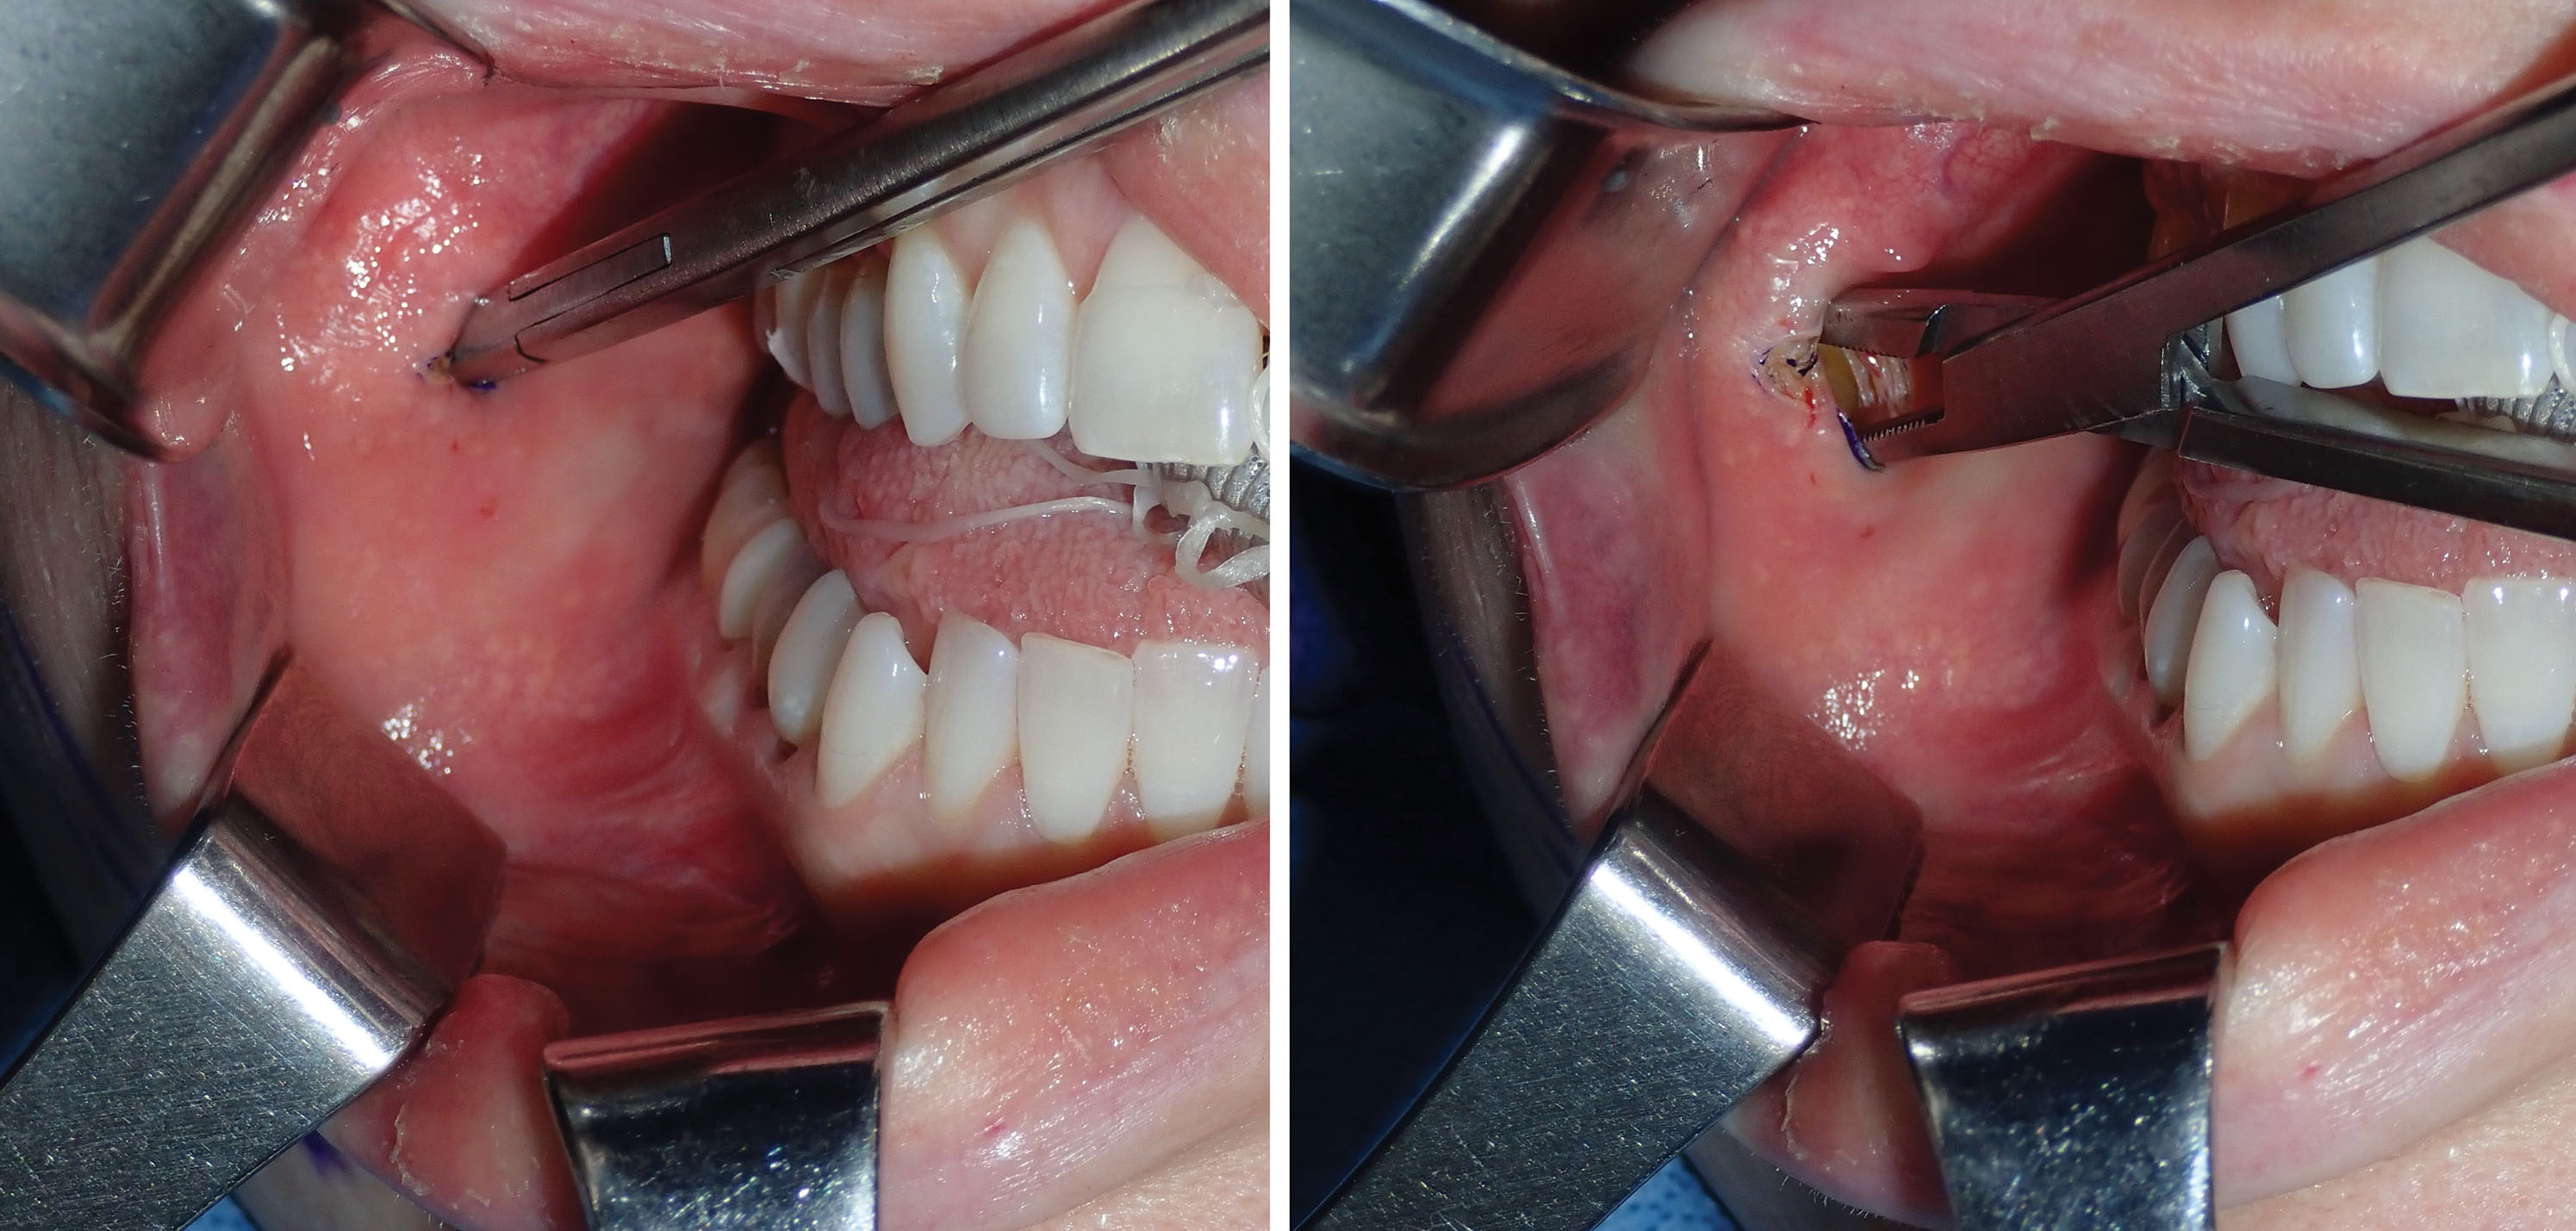

After the incision is made through the mucosa, a long, thin tonsil clamp is used to bluntly puncture through the buccinator muscle. This is a perfect instrument for atraumatic entry through the muscle, and the delicate curved tips are efficient to spread and grasp the fat pad. After the hemostat punctures the buccinator, the tips are spread within the buccal space, and the fat will frequently billow out of the incision ( Figs. 15.12 and 15.13 ). It is very common to secure a small lobe of the BFP, and once it is teased out of the capsule or incised, the other lobes pour out into the incision, much like blepharoplasty fat pads. As stated earlier, the parotid and buccal branches of the facial nerve traverse this area, so gentle manipulation is required ( Fig. 15.14 ).

Angling the hemostat slightly superolaterally can be helpful in locating the fat pad. Placing digital pressure on the cheek skin and manipulating the fat pad to the incision is helpful to capture the fat if it does not readily present ( Fig. 15.15 ). Once delivered, the fat pad is then secured with another pair of hemostats under slight traction ( Fig. 15.16 ). Usually this reveals more fat, and the second pair of hemostats is placed at the base and traction applied. This reciprocal procedure is repeated and allows the majority of the fat to be teased out of the capsule into the incision.